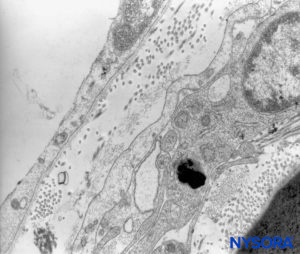

At the preganglion level, the cellular component of a root cuff is 5.8–13 μm thick. These cells have cytoplasmic prolongations that encroach on neighboring cells, leaving little extracellular space. Unions between cell membranes are of the type desmosome and have tight junctions (Figure 61). Cells contain mitochondria in their cytoplasm and rough endoplasmic reticulum. Each cell is about 0.15–0.8 μm thick at both ends and 2.2–4.9 μm at the nucleus. The cellular component is arranged in two concentric layers held apart by collagen fibers.

FIGURE 60. Human nerve root cuff. Detail of transition cellular barrier. Transmission electron microscopy. Magnification ×20,000. (Reproduced with permission from Reina MA, Villanueva MC, Machés F, et al: Ultrastructure of human spinal nerve root cuff in lumbar spine. Anesth Analg. 2008 Jan;106(1):339-344.)

FIGURE 61. Human nerve root cuff. Detail of transition cellular barrier. Transmission electron microscopy. Magnification ×3000. (Reproduced with permission from Reina MA, Machés F, Pulido P, López A, De Andrés JA. Ultrastructure of Human Spinal Meninges. In: Aldrete A. Arachnoiditis, Mexico: Alfil Ed; 2010. pp. 29-46.)